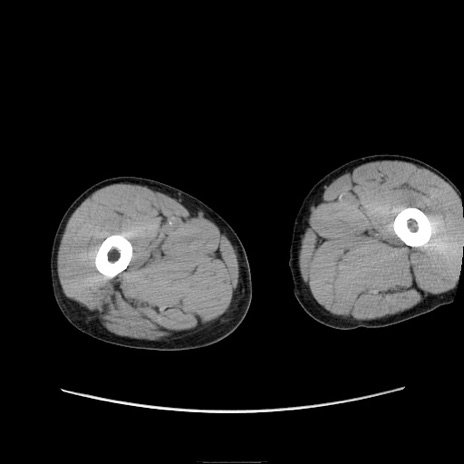

症例11(横断像)

【症例】 60歳代男性

【既往歴】 膀胱癌(膀胱全摘+尿管皮膚瘻術) 、胃癌術後

【身体所見】 BT 35.3℃、PR 58/min、BP 136/98mHg、腹部平坦、軟、腸蠕動音±、ストマ留置あり、左上腹部~正中部に圧痛あり、反跳痛なし。